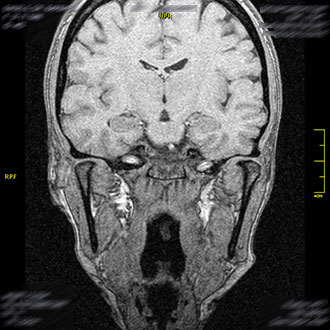

Die MRT des Gehirns ist zentral für die neurologische Diagnostik. Im Kernspin Zentrum Köln wird sie zur Abklärung verschiedenster Beschwerden eingesetzt – von häufigen Kopfschmerzen und Migräne bis zu komplexen neurologischen Erkrankungen.

Die MRT ermöglicht es, selbst kleinste Veränderungen im Gehirn frühzeitig zu erkennen – ein entscheidender Vorteil für eine gezielte Therapie.